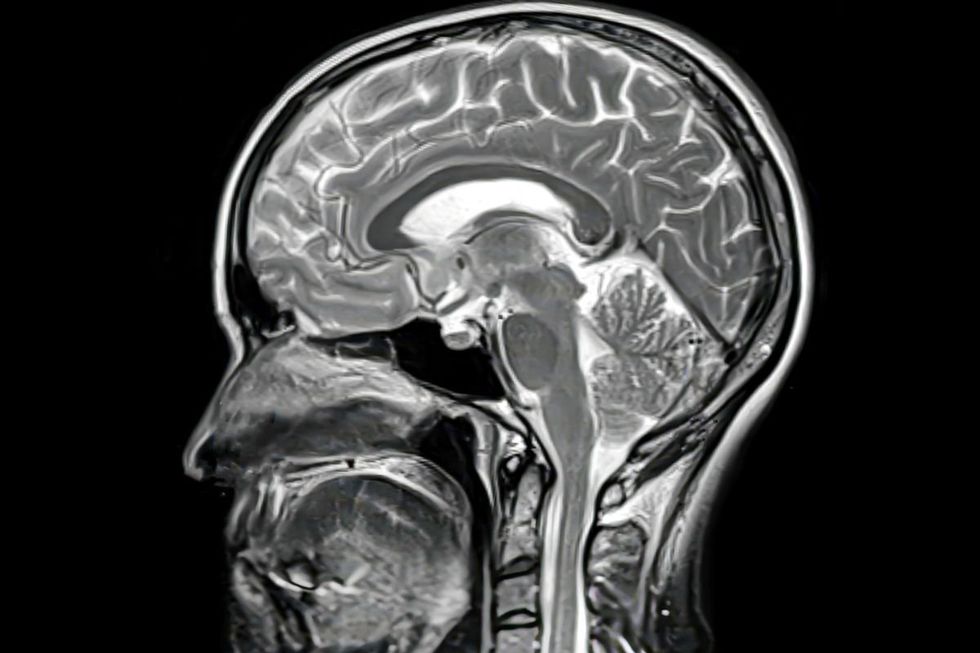

New findings have raised questions about the health benefits of fish oil for the brain

Fish oil has been hailed as one of the best supplements for brain health, but new findings have called this widely held belief into question.

The latest body of research looking at the neurovascular system has suggested that fish supplements could do more harm than good for certain people.

The findings, published in Cell Reports, suggest a specific chemical compound known as EPA could disrupt the brain’s healing process after an injury.

More specifically, it appeared to make the walls of the brain’s blood vessels less stable, presenting a challenge for blood vessels that need to repair themselves following an injury.

Fish oil disrupts repair signals put out by the brain after physical trauma, the researchers noted.

They also discovered a link between the supplement and a build-up of tau protein, which is linked to brain illnesses.

Fish oil may disrupt the repair process of the blood vessels in the brain